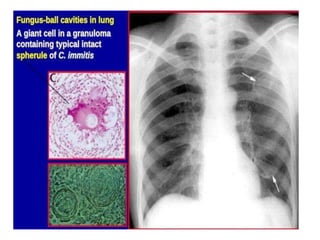

large (up to 80 micron) spherules/sporangia, as shown in this case.These are filled with

numerous spherical endospores.The sporangia and endospores can be within giant cells

or extracellularly.